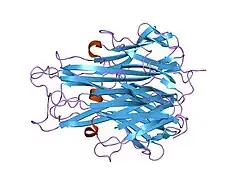

The secreted extracellular portion, denoted sTNF, consists of 157 amino acids.[22] Unlike tmTNF, sTNF can only bind to TNFR1.[10] The secondary structure of sTNF consists primarily of alternating strands that join into two sheets, known as antiparallel β-sheets. The two sheets are layered on top of each other, forming a wedge shape known as an antiparallel β-sandwich. Remarkably, this structure is similar to those seen on the coats of viruses. The last 9 residues of the C-terminus are locked into the middle strand of the bottom sheet, and are necessary for bioactivity.[22]

Both tmTNF and sTNF are only bioactive as homotrimers, whereas individual monomers are inactive.[10] The rate at which TNF trimers disassemble is constant, whereas the rate at which TNF trimers assemble increases with TNF concentration. This causes TNF to be mostly trimers at high concentrations, whereas TNF is mostly monomers and dimers at low concentrations.[23] The coexistence of TNF dimers and trimers in dynamic equilibrium suggests that TNF might be a morpheein.[24] Small molecules that stabilize TNF dimers and prevent the assembly of TNF trimers present a potential mechanism for inhibiting TNF.[25]